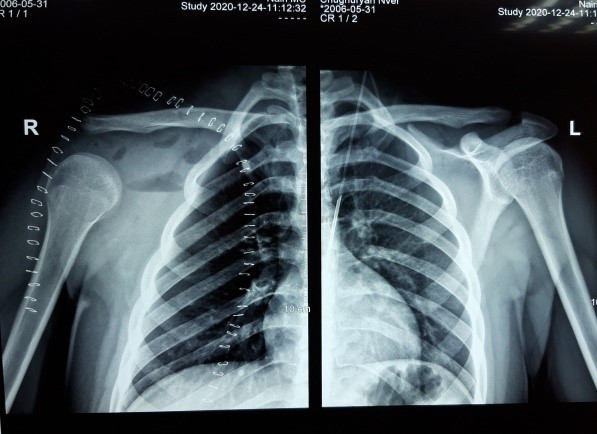

Նկար 2․ Վիրահատությունից հետո ` առկա է գերազանց էսթետիկ արդյունք